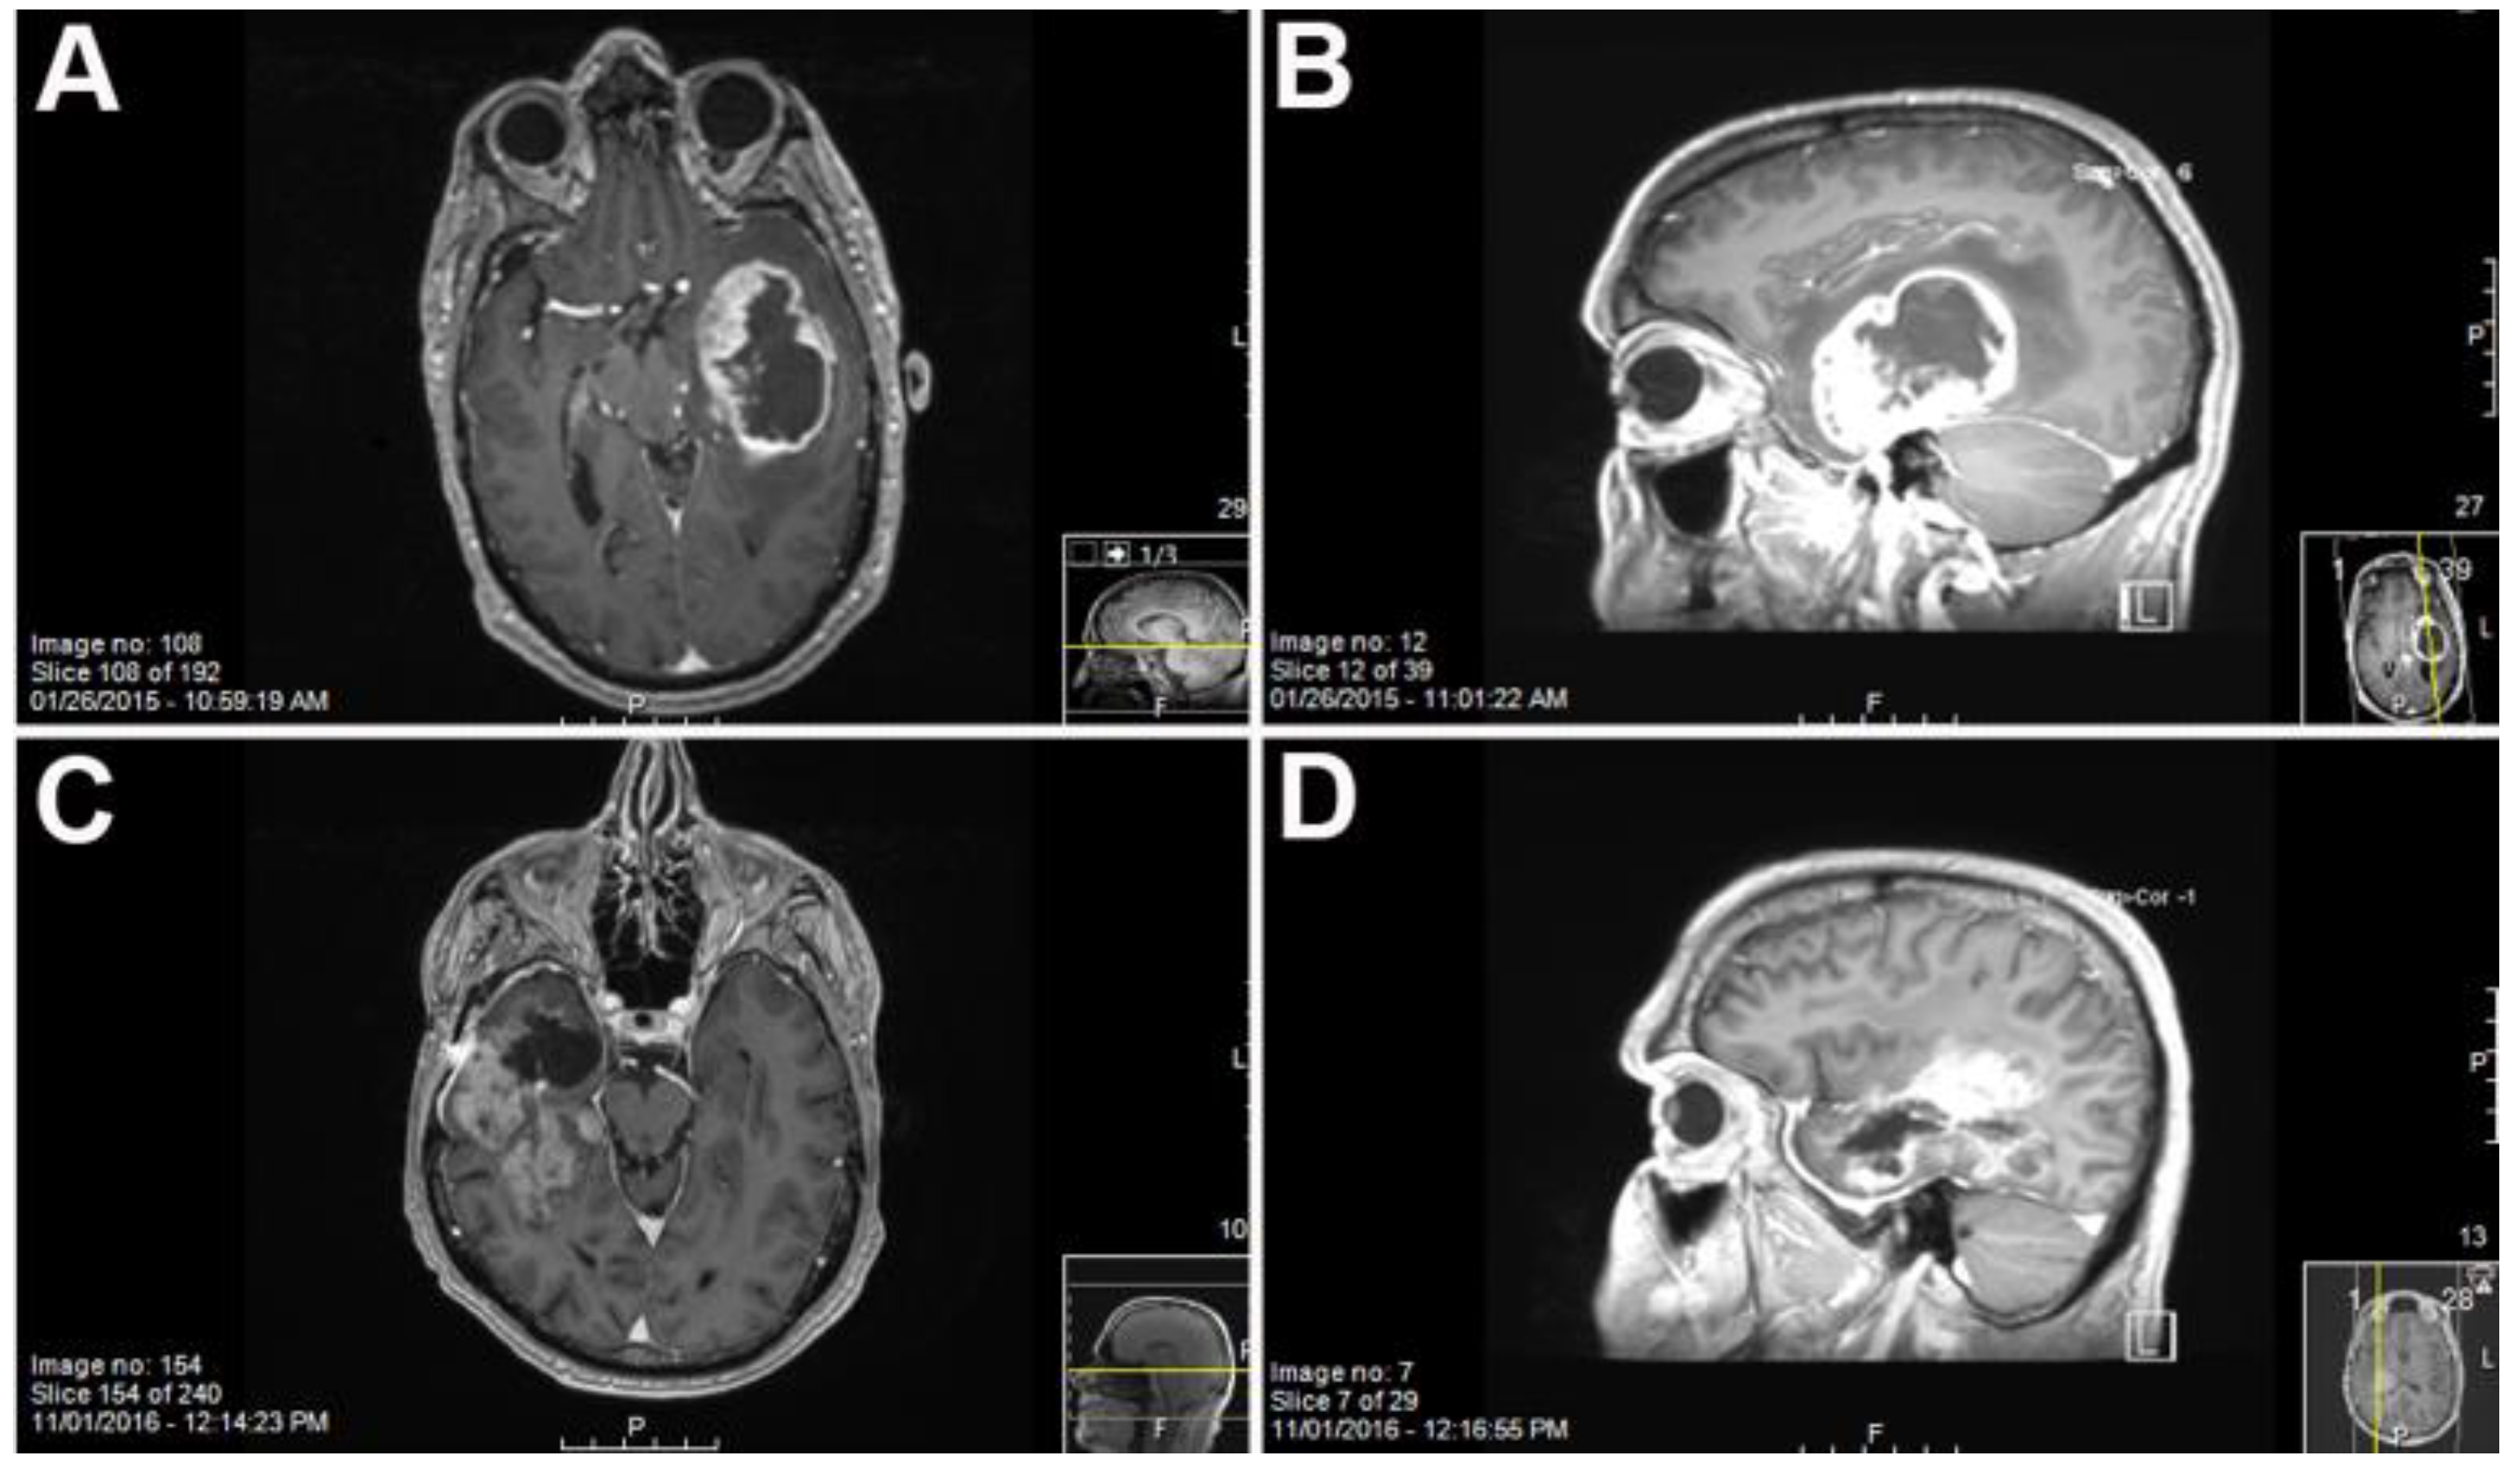

Figure 1.

MRI of patient 2025, a 58 year old male ((A) coronal and (B) sagittal) and patient 2409, a 57 year old male ((C) coronal and (D) sagittal) with T1 weighted gadolinium contrast showing the location of the Glioblastoma multiforme (GBM) prior to resection.